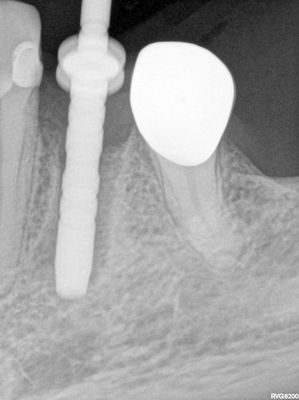

Atraumatic exo, about 2mm buccal bone loss, might have been present post exo but very thin, implant ostoetomy underprepared, dense bone at apex of socket, implant placed with good stabitliy, buccal flapped, socket and buccal grafted with allograft (small amount of xeno) folloewd by collagen membrane, healing abutment placed

PB170018.JPG